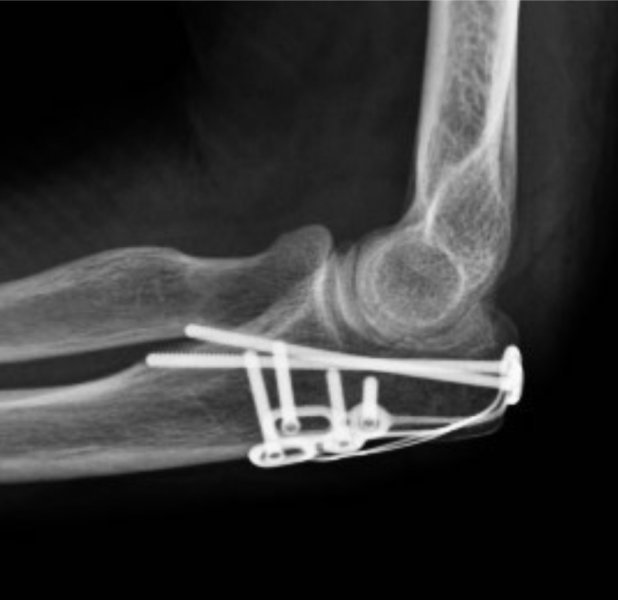

The operation is performed under a combination of general and regional anaesthesia. The fracture is exposed, the bone fragments realigned and then fixed with screws, a plate and screws or tension band wires.

An appointment will be arranged for you to be seen at 2 weeks after the procedure.  Follow-up may be required for at least 6-12 months after surgery or until a satisfactory recovery is achieved. X-rays will be performed at intervals to monitor fracture healing.